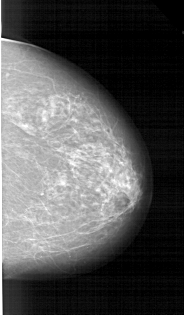

A_1214_1.RIGHT_MLO